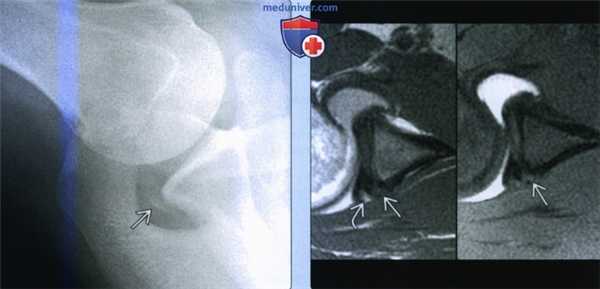

(Слева) На аксиллярной рентгенограмме видна оссификация по заднему краю суставной впадины у бейсбольного питчера.

(Справа) На осевой МР-артрограмме Т1ВИ и МРТ Т1ВИ FS у этого же пациента определяется неоднородный сигнал, соответствующий участку оссификации. Участок высокоинтенсивного сигнала на томограмме без жироподавления может соответствовать желтому костному мозгу. Более того, у пациента имеется внутренний импиджмент с разрывами губы и манжеты и поэтому, предполагалось, что повреждение Беннетта не вызывало болевой синдром.